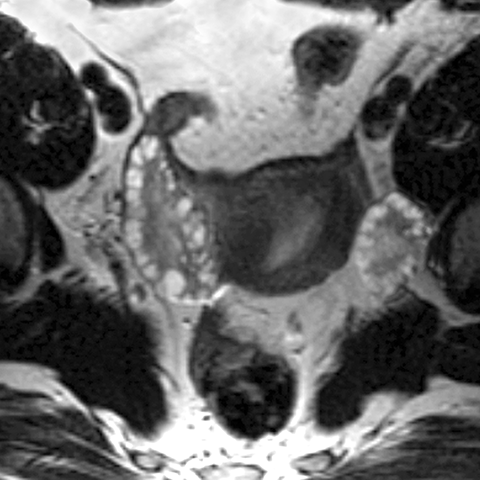

Ovary (T2 weighted MR)